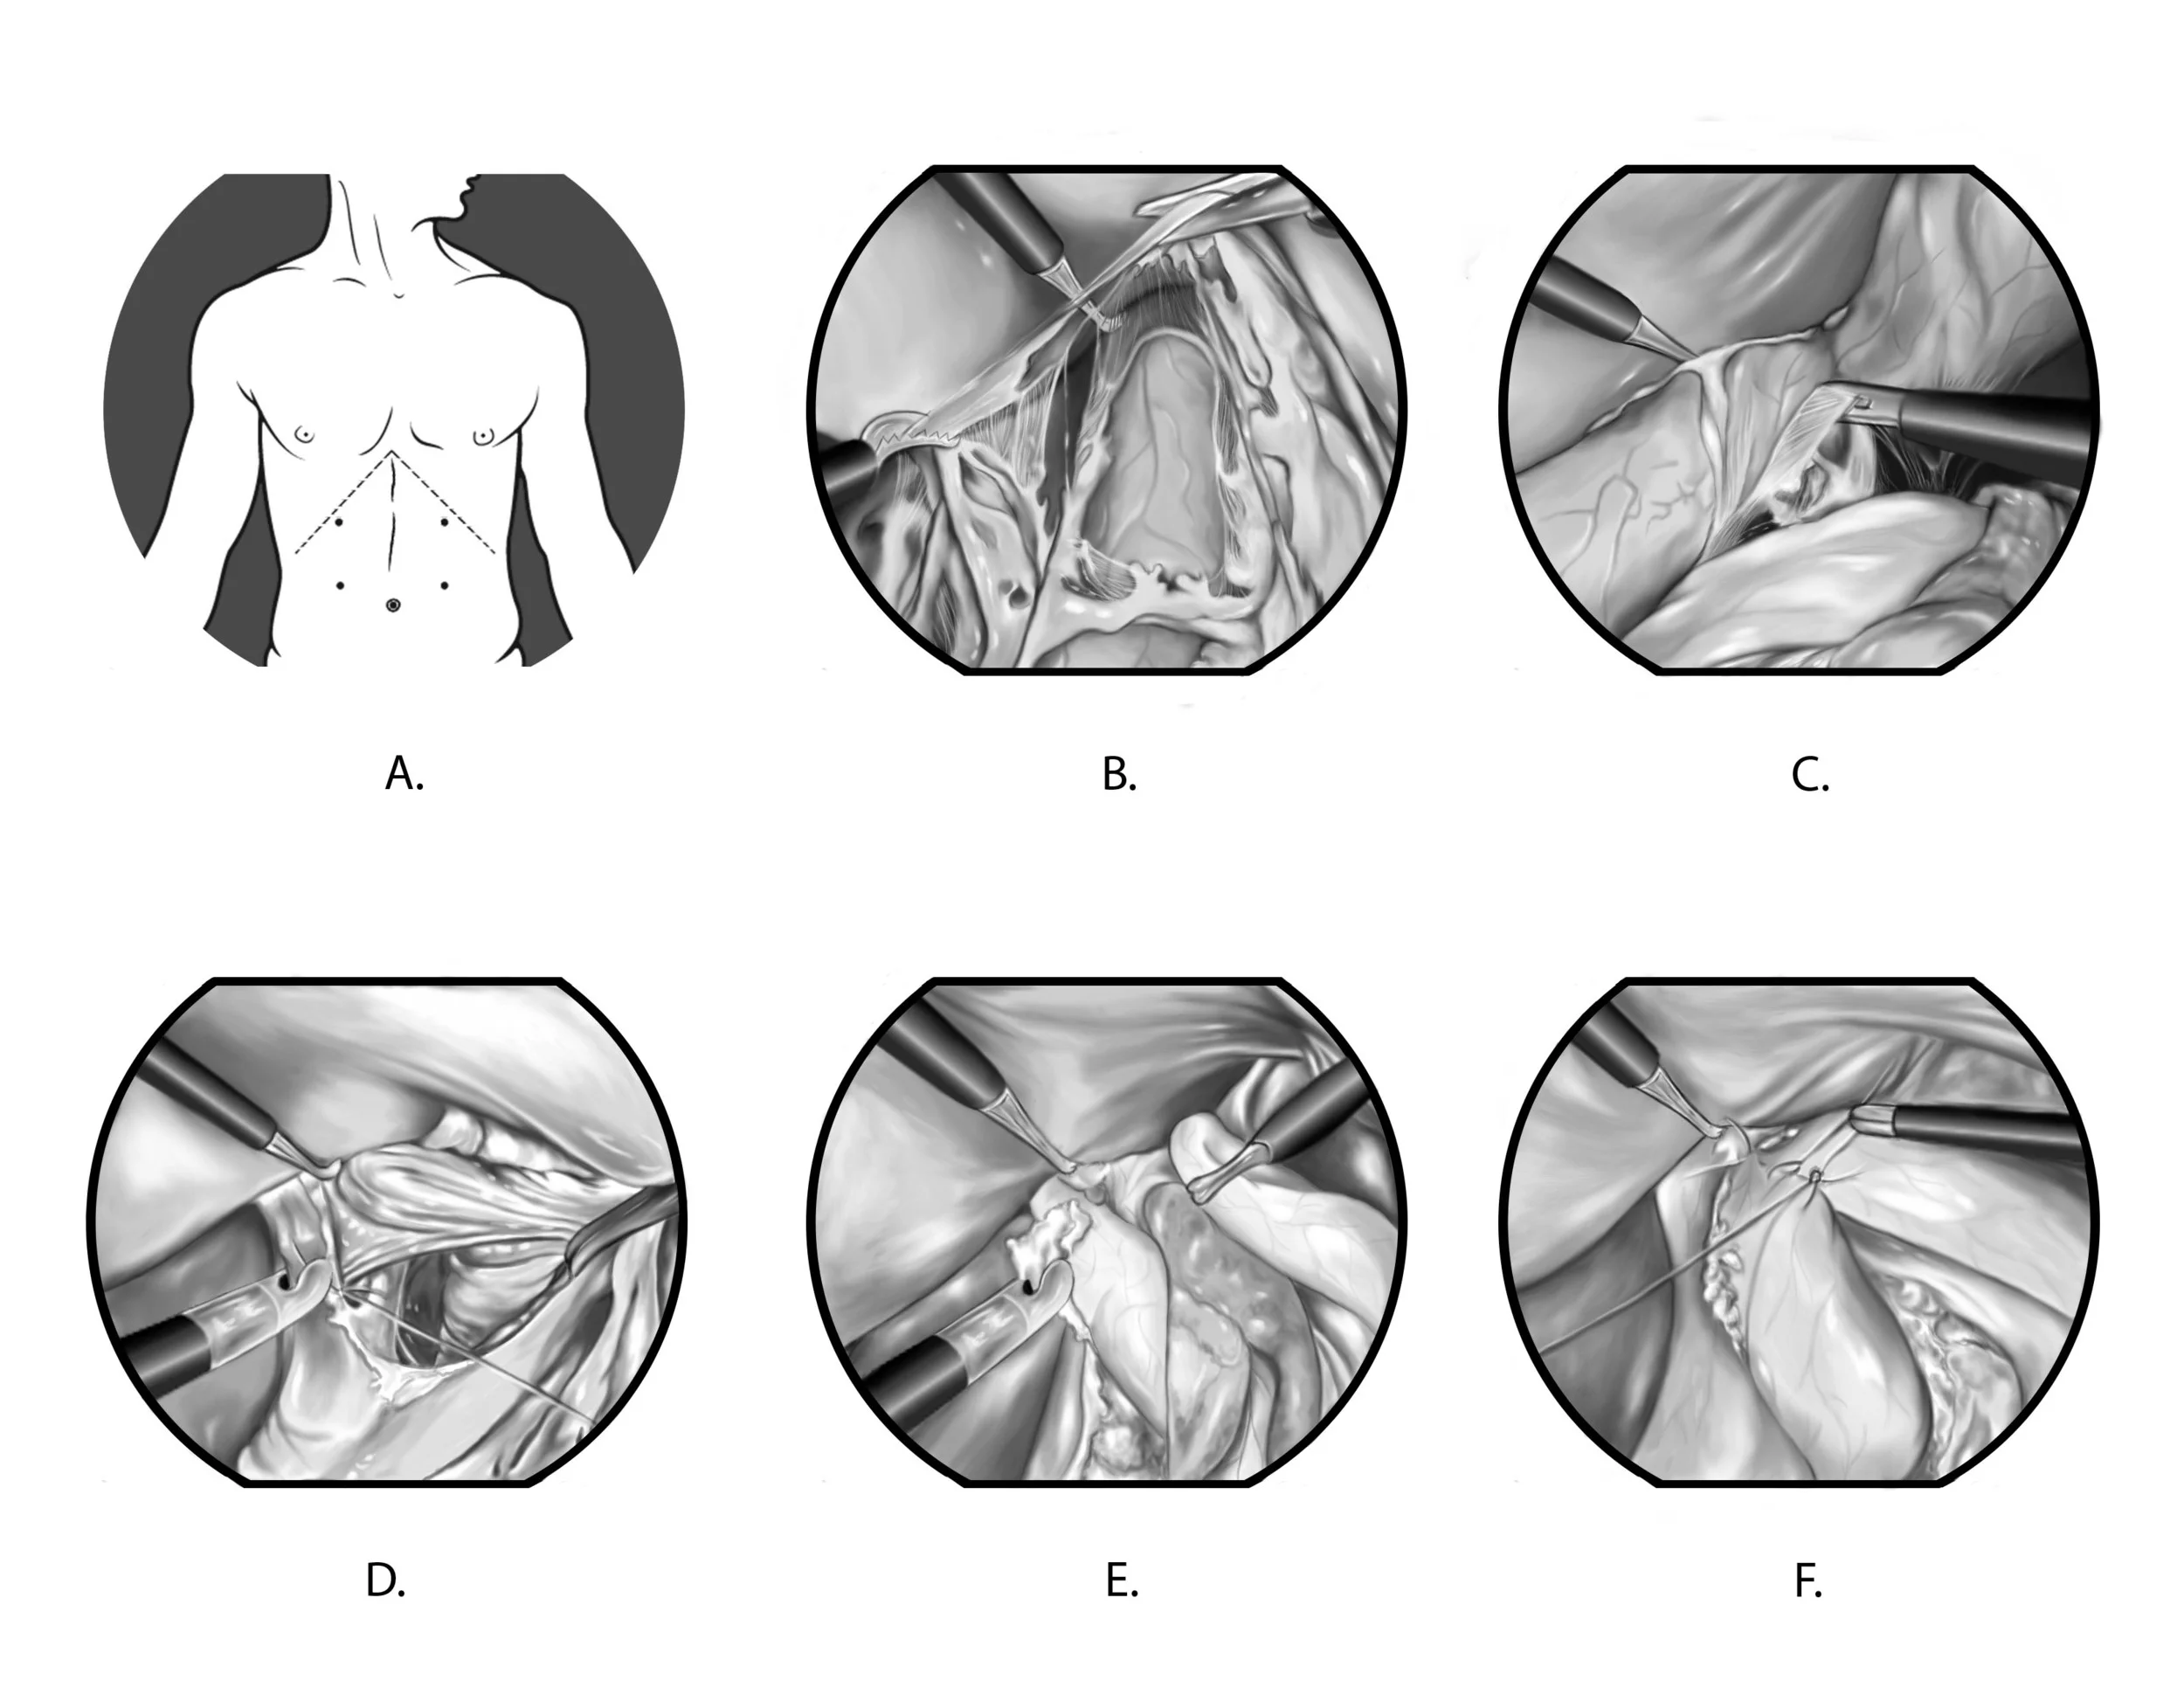

Biomedical art is a form of biological illustration that helps record and disseminate medical, anatomical, and related knowledge. It translates complex technical medical information into visual artwork to support research, patient care and education, public relations, and marketing objectives.